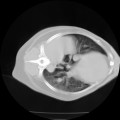

CT